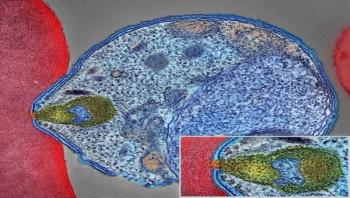

Researchers from the National Institute of Allergy and Infectious Diseases (NIAID), part of the National Institutes of Health, modified an experimental malaria vaccine and showed that it completely protected four of eight monkeys that received it against challenge with the virulent Plasmodium falciparum malaria parasite. In three of the remaining four monkeys, the vaccine delayed when parasites first appeared in the blood by more than 25 days.